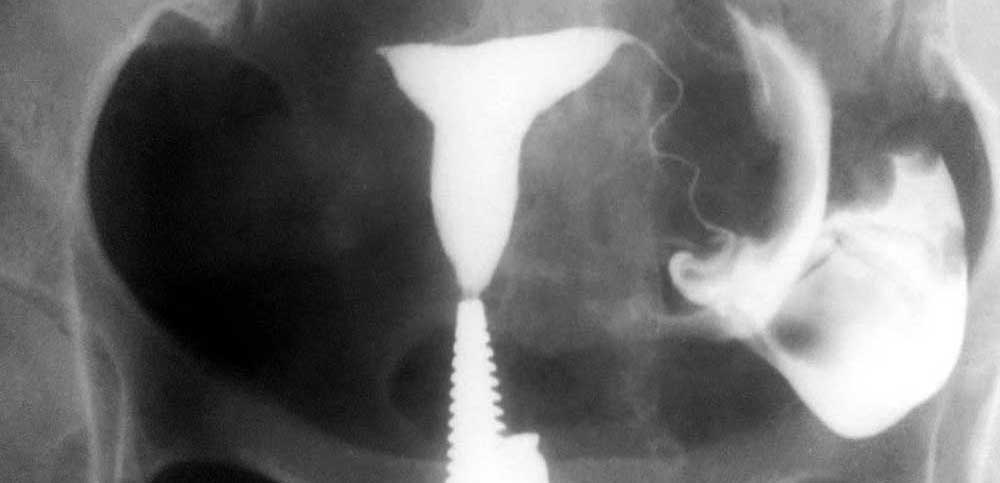

هیستروسالپنگوگرافی؛ هیستروسالپنگوگرافی (HSG) نیز نامیده می شود، هیستروگرافی یک معاینه اشعه ایکس از رحم و لوله ها است. در سال های اخیر، به طور فزاینده ای با تصویربرداری رزونانس مغناطیسی (MRI) جایگزین شده است. هیستروگرافی در مطب رادیولوژی توسط رادیولوژیست انجام می شود.

این معاینه امکان مشاهده حفره رحم و لوله های فالوپ را در صورت بروز مشکلاتی در شروع بارداری یا وجود خونریزی که منشا آن با سونوگرافی مشخص نمی شود را ممکن می سازد. با این حال، اندیکاسیون های این معاینه در حال حاضر با تمرین گسترده سونوگرافی و سایر تکنیک های تصویربرداری (MRI و غیره) کاهش یافته است.

هیستروسالپنوگرافی یک معاینه رادیوگرافی برای مشاهده رحم (= هیسترو) و لوله های فالوپ (= سالپنگو) با استفاده از یک محصول غیر شفاف نسبت به اشعه ایکس، تزریق شده به داخل حفره رحم است.

بیمار در وضعیت زنان (به پشت خوابیده، زانوهای خم شده و از هم باز)، زیر دستگاه اشعه ایکس قرار می گیرد. پزشک یک اسپکولوم را وارد واژن میکند، سپس یک کانولا را در دهانه رحم قرار میدهد که از طریق آن یک ماده حاجب تزریق میکند. این به داخل رحم و لوله های فالوپ گسترش می یابد. اشعه ایکس برای مشاهده پیشرفت خوب محصول و تجسم اندام ها گرفته می شود.

تعریف هیستروسالپنگوگرافی چیست؟

این یک معاینه اشعه ایکس از رحم و لوله های فالوپ است. هدف آن کاوش حفره و لوله های رحمی برای جستجوی ناهنجاری است. به لطف تزریق ماده حاجب به داخل حفره رحم، هیستروسالپنگوگرافی (HSG) نفوذپذیری لوله ها، طبیعی بودن حفره رحم و پراکندگی محصول در حفره صفاقی را تایید یا باطل می کند.

هیستروسالپنگوگرافی امکان مات کردن و کاوش کانال اندوسرویکال و مسیر آن، حفره رحم، دهانه های داخلی لوله ها (ostia tubaires)، لوله های رحمی، دهانه های خارجی لوله ها و حفره صفاقی را فراهم می کند. هیستروسالپنگوگرافی اجازه کاوش تخمدان ها را نمی دهد.

هیستروسالپنگوگرافی توسط رادیولوژیست انجام می شود. معاینه بدون بیهوشی انجام می شود. بیمار در موقعیت "زنان و زایمان" مستقر می شود. پزشک اسپکولوم را قرار می دهد، دهانه رحم را ضد عفونی می کند و سپس یک پروب را با روش طبیعی وارد رحم می کند. او به تدریج ماده حاجب را تزریق می کند. به طور معمول، ماده حاجب به تدریج رحم و لوله های فالوپ را کدر می کند تا زمانی که به حفره صفاقی منتقل شود.

چندین عکس رنگی رحم قبل، حین و بعد از تزریق محصول گرفته می شود و این در موقعیت های مختلف:

اشعه ایکس بدون آماده سازی (جستجو برای کلسیفیکاسیون لگن)؛

اشعه ایکس پر شدن ضعیف (پولیپ ها یا فیبروم های زیر مخاطی را برجسته می کند).

اشعه ایکس پر شدن لوله (ارزیابی وضعیت مخاط لوله).

عکس پروفایل (ارزیابی موقعیت رحم و مسیر لوله های فالوپ)؛

اشعه ایکس دیررس (بررسی گردش خون صفاقی، جستجو برای چسبندگی لگن).

در اصل، HSG یک ارزیابی رادیوگرافی از حفره رحم و لوله های فالوپ با استفاده از فلوروسکوپی سرپایی بلادرنگ با تزریق ماده حاجب رادیویی مات از طریق کانال دهانه رحم را نشان می دهد. کانال دهانه رحم، کانتور حفره رحم و لومینای رحم و لوله شامل بخش های قرنیه، ایستمی و آمپولری و تعیین